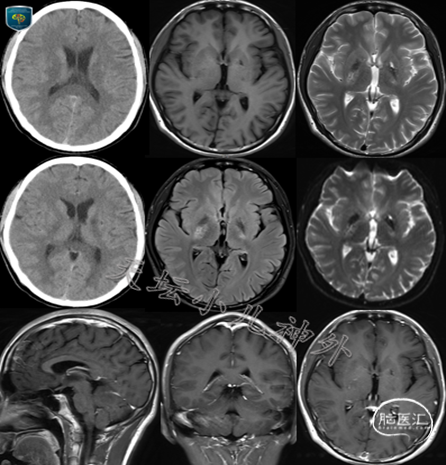

我院神经内科神经肌肉病区发来会诊申请一例,17岁男性患儿,北京市人(身高:182cm,体重:73kg),主诉:疲劳乏力1年,右侧肢体无力伴饮水呛咳3个月持续不缓解。查体:神情语利,自主体位,咽反射稍减弱,右上肢指鼻、轮替试验(+),右下肢远端肌力IV级,余肌力肌张力正常,外阴发育正常。否认多饮多尿史,近一年学习成绩减退明显。头颅CT示:双侧基底节区多发斑点状低密度灶,局部边界不清;头颅MRI示:右侧内囊后肢及丘脑多发斑点、斑块状长T1长T2信号影,左侧基底节区见斑点状长T1长T2信号影。双侧内囊丘脑异常信号,不除外中枢神经系统血管炎。(图1);肿瘤标记物:血清β-HCG:47.06mIU/ml(正常值:<2mIU/ml),脑脊液β-HCG:74.14mIU/ml(正常值:<2mIU/ml)。神经内科初步考虑中枢神经系统血管炎,为除外基底节区生殖细胞瘤,特请我科会诊。

图1 头颅CT示:双侧基底节区多发斑点状低密度灶,局部边界不清;头颅MRI示:右侧内囊后肢及丘脑多发斑点、斑块状长T1长T2信号影,左侧基底节区见斑点状长T1长T2信号影。双侧内囊丘脑异常信号,不除外中枢神经系统血管炎。